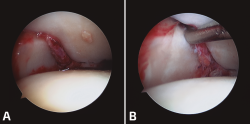

En los casos crónicos, en los que la inestabilidad se asocia a desaxaciones en el plano axial, será necesario realizar osteotomías correctoras. La visión artroscópica nos ayudará a la reducción articular y estabilizaremos la sindesmosis. (Figura 4).

Figura 4. A: sindesmosis inestable; B: sindesmosis estabilizada.